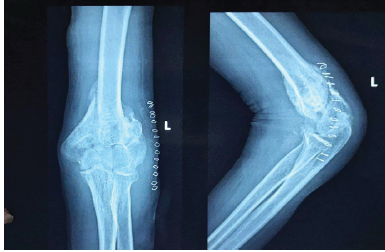

Challenges in Management of a Post-Traumatic Stiff Elbow – When to Perform Open Arthrolysis: A Case Report

Adithyaa S , Tarun Prashanth K R , M R Thirunthaiyan , R Dorai Kumar , B Sundararaja

………………………………p.74-79